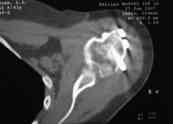

закрытый оскольчатый перелом проксимального отдела левой плечевой кости со смещением отломков (b1_xr.jpg). 06.04.2007 оперирована в одном из отделений: открытая репозиция, накостный остеосинтез проксимального отдела левой плечевой кости. Выписана с заключительным диагнозом: а)основной: закрытый 4-х фрагментарный (по Ниру) перелом проксимального отдела левой плечевой кости, со смещением отломков; б) осложнения основного: нейропатия левого локтевого нерва; в) сопутствующий: миокардитический миокардиосклероз ХСН 0-1.

В момент осмотра: нормостеническая конституция, по передней поверхности плечевого сустава – рубец. Рука в положении приведения. Отведение не более 10 град, дальнейшие движения с лопаткой до 20-25 град. Амплитуда сгибания-разгибания 10-15 град. Ротация отсутствует. Пальпаторно - выраженная болезненность над суставом, особенно в проекции клювовидного отростка. При попытках пассивных движений – боль. Рентгенограммы и результаты КТ приложены(b2(3)_xr.jpg, b1(6)_ct.jpg).